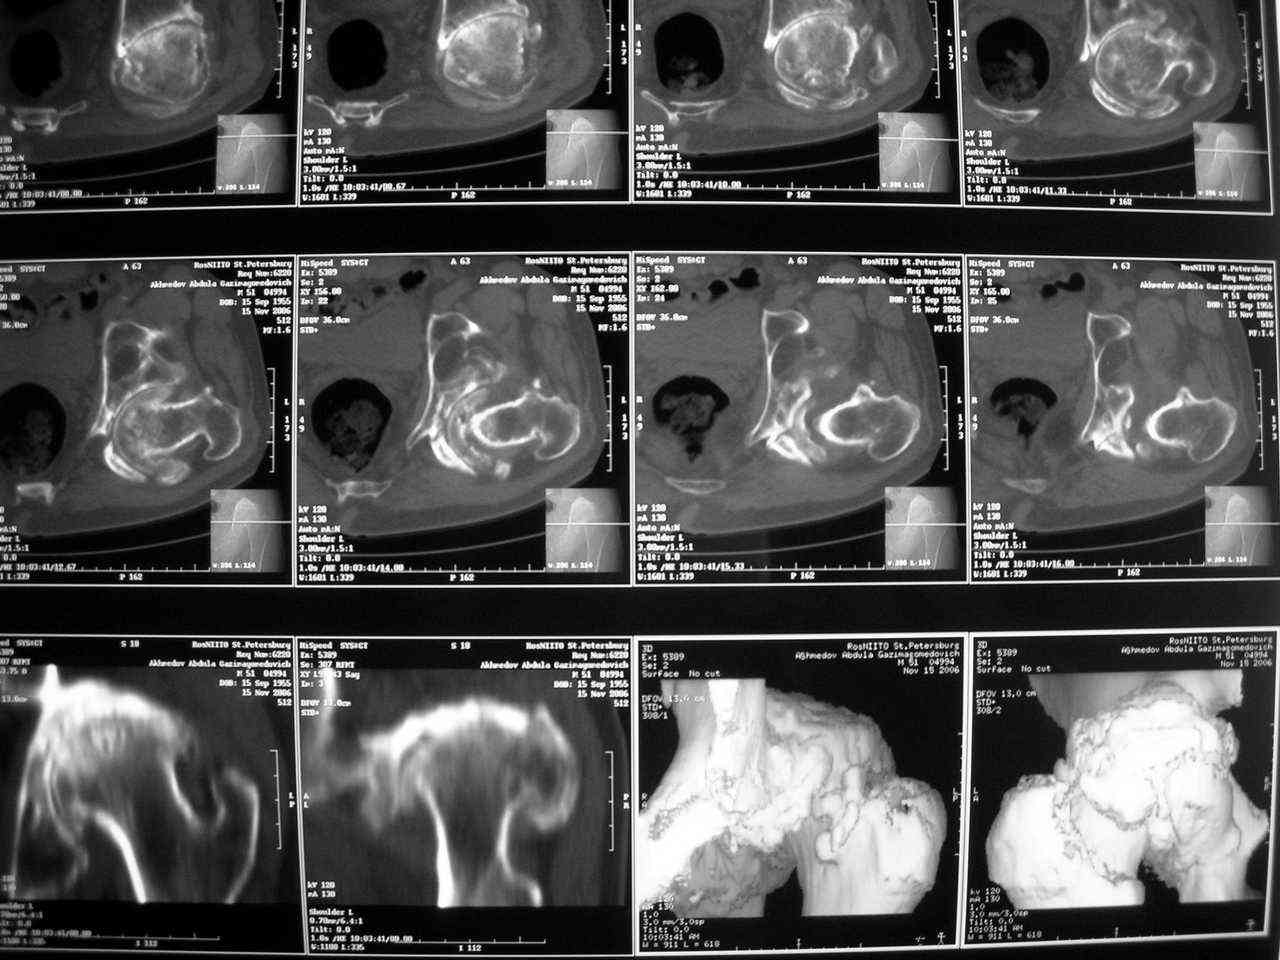

Прилагаю в качестве иллюстрации одну из последних операций.

Еще одно наблюдение, неправильно сросшийся перелом заднего отдела ВВ с ввихом головки бедра 16-и летней давности.

Кстати, судя по рентгенограммам и КТ истинная разница в длине ног не столь велика, укорочение, главным образом, за счет контрактур.